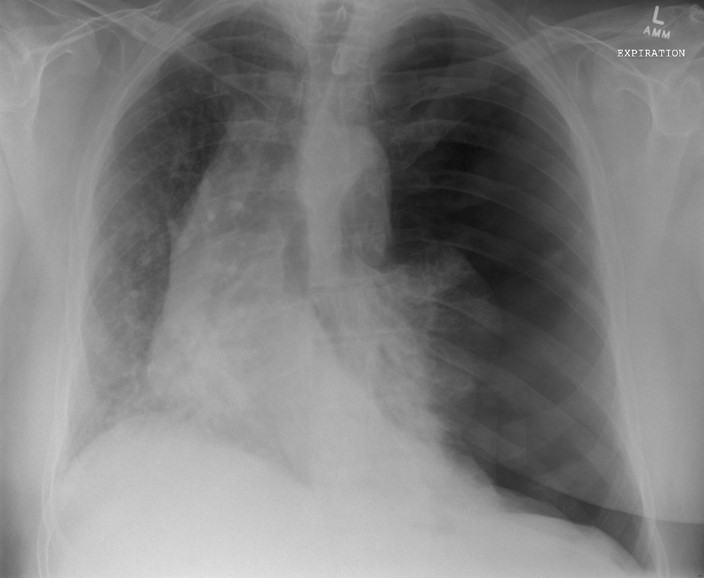

Spontaneous Pneumothorax

(well demarcated line, right side is super black bc no lung tissue there)